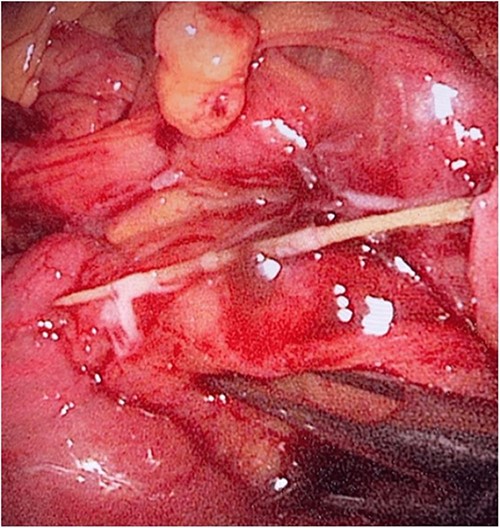

During her hospital stay, the patient showed no improvement regarding abdominal pain, nausea, or abdominal exam. Therefore, she was offered a laparoscopic exploration to verify the diagnosis of a FB to which she agreed. She was taken to the operating room, and the exploration showed an inflammatory process in the LLQ (Fig. 3) with the sigmoid colon attached to the area of the inflammatory reaction. A FB was found in the mesentery of two loops of the ileum 100 cm from the ileocecal junction (Figs 4 and 5). Removal of the FB safely and milking of the small bowel showed no leakage of bowel contents (Fig. 6). And, exploring the rest of the abdomen showed no other pathology and normal ovaries (Figs 7 and 8); the procedure was uneventful. The FB was identified as a toothpick, 3 cm in length (Fig. 9).

The laparoscopic exploration showed a FB in the mesentery of two loops of the ileum 100 cm from the ileocecal junction—after full exposure of the site of the toothpick.